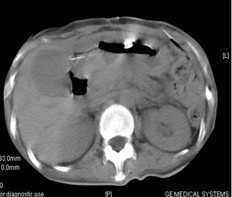

女,49歲。胃體癌晚期,胃竇增厚強(qiáng)化,與周?chē)尺B,腹膜增厚,腹腔廣泛轉(zhuǎn)移,伴大量腹水。放/化療失敗,無(wú)法手術(shù)。治療方案:腹腔灌注今又生2×1012VP/2次/周,共12周,同時(shí)灌注順鉑和5-氟尿嘧啶腹腔,后4周加8次全腹熱療。治療后:第3周,腹水消失;第8周,胃竇、腹膜和網(wǎng)膜變薄,盆腔結(jié)節(jié)明顯變小。后行手術(shù)切除殘余胃腫瘤,術(shù)中探查全腹和盆腔未捫及腫瘤。術(shù)后病檢胃腫瘤內(nèi)未見(jiàn)癌細(xì)胞。

治療前胃竇增厚強(qiáng)化,與周?chē)尘o,腹膜增厚,大量積水